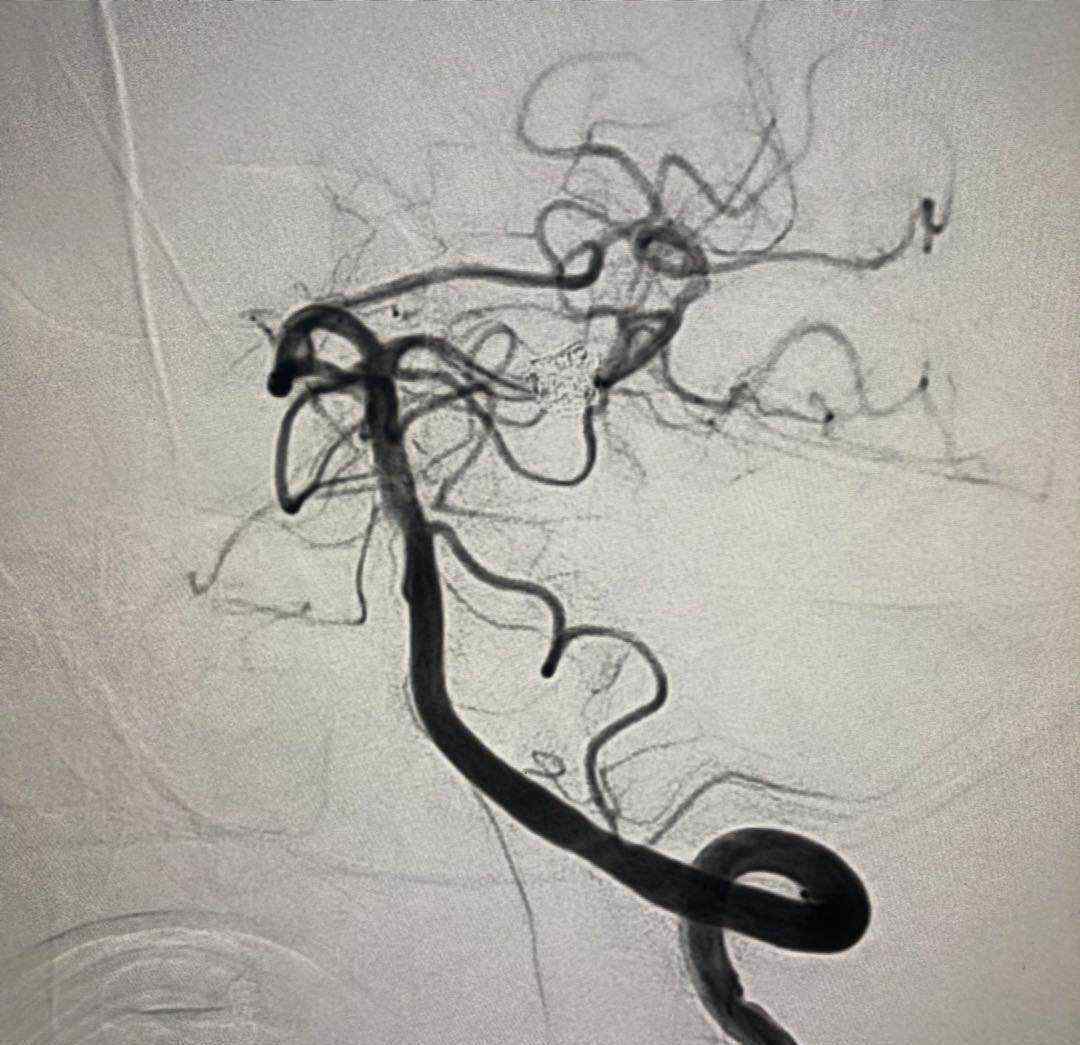

于2019.4.18日行颅内动脉瘤栓塞术

术后患者神清语明,四肢无瘫